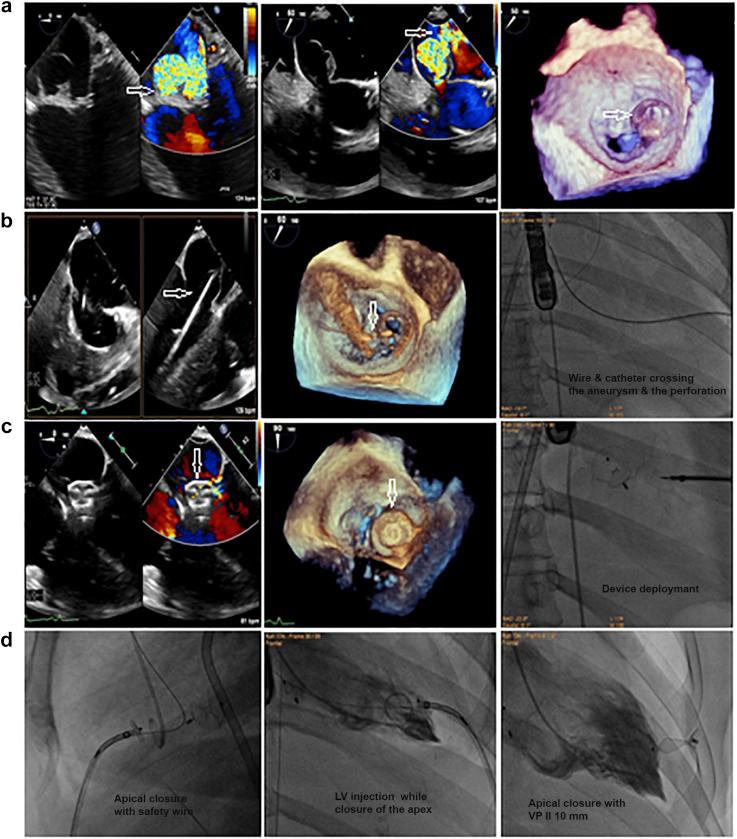

The study enrolled 16 patients; 9 (56.25%) with MVL perforations and 7 (43.75%) with post-MitraClip (Abbott Laboratories, Abbott Park, Illinois) residual MR, with a mean age of 55.75 ± 16.69 years. Mean perforation/jet diameters were 5.75 ± 1.67 and 6.5 ± 1.93 mm, and the mean 3D-vena contracta area was 0.54 ± 0.14 cm. Perforations were crossed retrograde (transaortic in 7 [43.75%] patients and transapical in 2 [12.5%] patients), and post-MitraClip devices residual jets were crossed antegrade (transvenous/transseptal). Six (37.5%) patients required arteriovenous loop formation for device deployment, that was antegrade transvenous/transseptal in 13 (81.25%) patients and retrograde transapical in 3 (18.75%) patients. Devices used were Amplatzer-ASO in 10 (62.5%) patients and Amplatzer-VP-II in 6 (37.5%) patients. Mean procedural and fluoroscopy times were 55.13 ± 16.24 and 16.25 ± 4.03 ​minutes, respectively. Patients passed successfully, without MV gradient change or device-related complications.

本研究共纳入16例患者;9例(56.25%)为MVL穿孔,7例(43.75%)为MitraClip(雅培实验室,伊利诺伊州雅培公园)夹闭术后残留MR,平均年龄为55.75±16.69岁。穿孔/射流平均直径分别为5.75±1.67和6.5±1.93mm,平均三维缩流颈面积为0.54±0.14cm²。穿孔采用逆行穿过(7例[43.75%]经主动脉,2例[12.5%]经心尖),MitraClip装置术后残留射流采用顺行穿过(经静脉/经房间隔)。6例(37.5%)患者需要形成动静脉环以部署装置,其中13例(81.25%)患者采用顺行经静脉/经房间隔,3例(18.75%)患者采用逆行经心尖。使用的装置为10例(62.5%)患者使用Amplatzer-ASO,6例(37.5%)患者使用Amplatzer-VP-II。平均手术时间和透视时间分别为55.13±16.24分钟和16.25±4.03分钟。患者均顺利通过,未出现MV梯度变化或与装置相关的并发症。